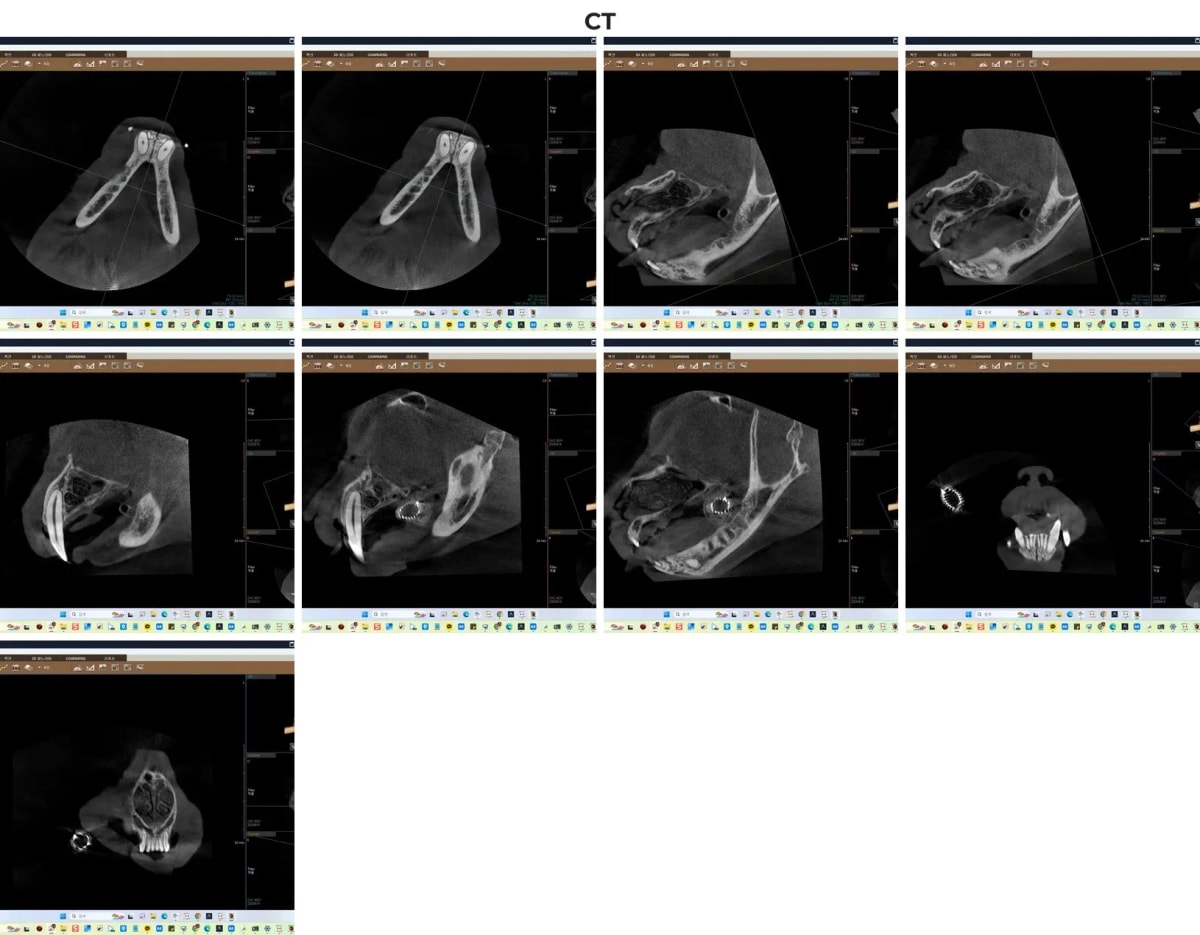

2. 정확한 진단을 위한 치과 전용 CT 촬영

치과 질환은 눈으로 보이는 잇몸 부종이나 잇몸 출혈 외에도 치아 뿌리와 턱뼈 내부에서 진행되는 병변을 파악하는 것이 필수적입니다. 겨울이의 경우, 잔존해 있는 치아 중 추가적인 발치가 필요한 치아를 정확히 선별해야만 만성적인 염증의 고리를 끊어낼 수 있었습니다.

ℹ️ 치과 CT의 중요성

광주 전남 유일 치과 CT를 활용하면 2차원 구강 방사선으로는 확인하기 어려운 미세한 병변이나 치조골 흡수(잇몸뼈가 녹는 현상) 양상을 3차원으로 입체적으로 파악할 수 있습니다. 이를 통해 남겨진 치아를 보존할지, 발치할지 명확한 기준을 세울 수 있습니다.

겨울이의 치과 전용 CT 촬영 영상